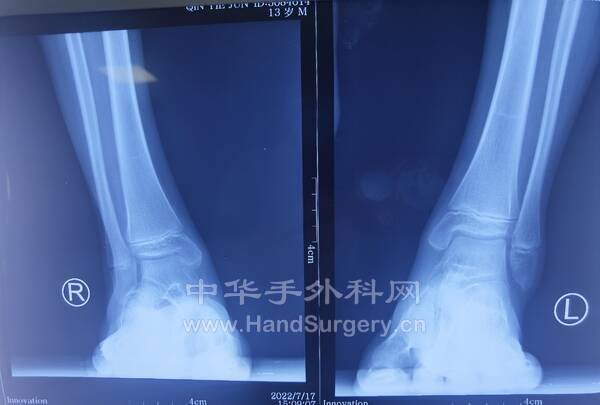

2022-7-24~7-25门诊知识点

病例,男,19岁,身高196cm,体重100kg,左舟骨骨折术后1年,内置物折断

9.距骨缺血性坏死患者,如果体重超正常体重,建议其减重后再行手术治疗。(5--8)